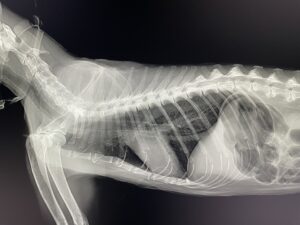

レントゲンがデジタルDRになりました!

今までフィルムが画像がきれいに撮れるということで、フィルムでの撮影を続けてきていたのですが、この度 デジタルのDRを導入することにしました。

DRは撮影からパソコンへ画像が映るまでにわずか5秒で出るという優れものであります。

画像も非常にきれいで 満足いく結果になっています。

獣医業界では最高クラスのピクセルサイズ(100μm 1500万画素)の細かさを誇る製品です。

より精度の高いレントゲン撮影が短時間でできるようになりました。

2025年10月3日 導入